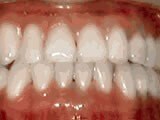

Patient sucked her thumb as a young child. She started treatment at age 13. She had braces and a special appliance — called a crib — to retrain the tongue, for 28 months. Now she can bite the lettuce out of a sandwich.